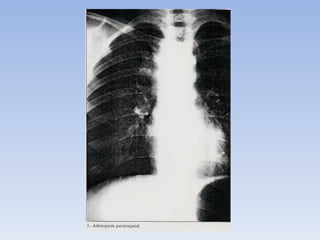

TBC PRIMARIA :

PRESENTACIÓN GANGLIONAR :

• las adenopatías es prácticamente

patognomónica de la fase primaria de la

enfermedad, (90%)

• el grupo mas frecuentemente afectado es el

traqueo bronquial derecho.

• La combinación de una lesión neumónica

lobar con adenopatías es muy típica de

tuberculosis (complejo primario)

Adenopatías a nivel del hilio pulmonar derecho, manifestación de tuberculosis primaria. El

diagnostico diferencial debe considerar linfoma y Cá. pulmonar.